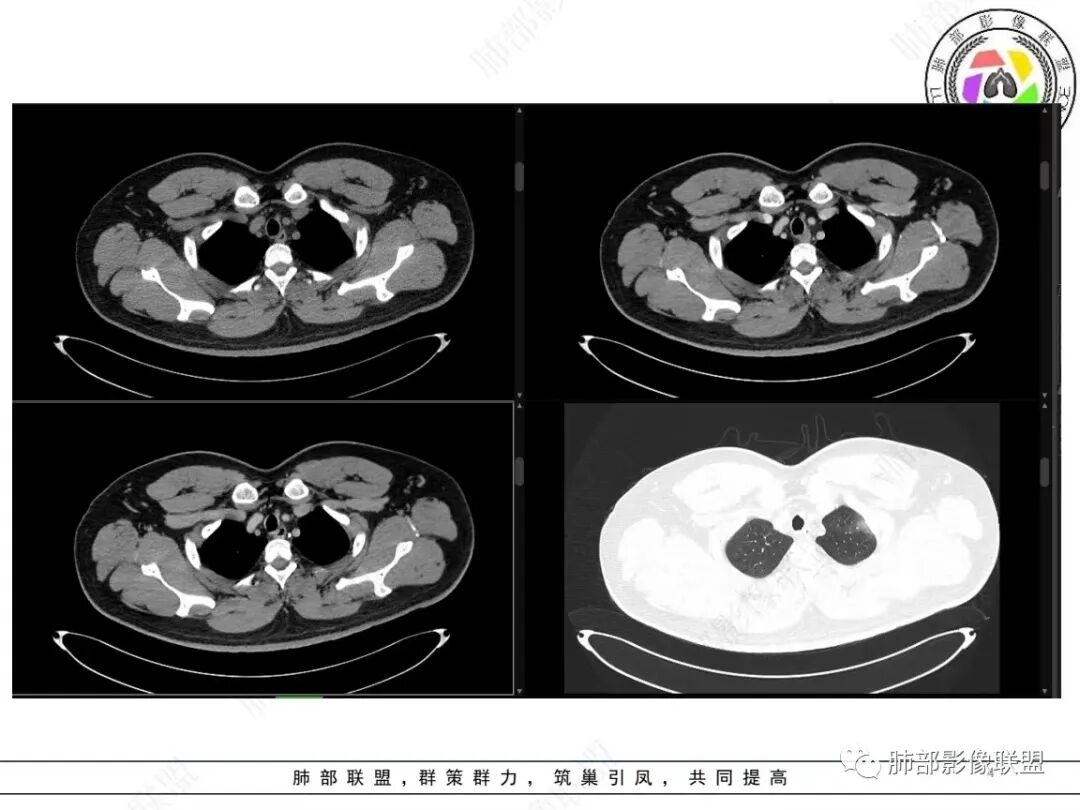

左上肺软组织肿块,周围散在磨玻璃影,界不清,窄基底贴于胸壁,胸膜下脂肪间隙不清,呈低强化,胸膜下见。与主病灶强化方式一样的病变,2R区见肿大淋巴。考虑恶性,间叶组织来源合并出血。

青年男性,咯血;CT示左肺上叶胸膜下软组织肿块,边界尚清,宽基底与胸膜相连,增强动脉期内见细条状血管影,轻度延迟强化,定位:肺外,胸膜外脂肪存在,考虑脏层胸膜起源;定性:考虑SFT。

有血供,强化不明显,周围肺出血,肺组织受压改变,定位肺外,胸膜增厚,部分胸膜下脂肪间隙存在,不确定肋骨是否受侵犯,部分层面与肺动脉分界不清,感觉推移,如果供血要考虑sft,强化不符合,有血管进入,但是强化不明显,密度相对均匀,所以不考虑坏死,富含粘液可能,咯血,说明累及支气管了,有一定侵袭性,肿块大,考虑间叶来源肿瘤,与胸膜接触面相对不是宽基底,综合考虑滑膜肉瘤可能,典型的滑膜肉瘤一般铺路石改变,这个又觉得信号相对均匀了一些学习中